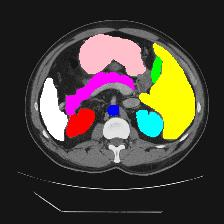

Medical image segmentation is one of the most fundamental tasks concerning medical information analysis. Various solutions have been proposed so far, including many deep learning-based techniques, such as U-Net, FC-DenseNet, etc. However, high-precision medical image segmentation remains a highly challenging task due to the existence of inherent magnification and distortion in medical images as well as the presence of lesions with similar density to normal tissues. In this paper, we propose TFCNs (Transformers for Fully Convolutional denseNets) to tackle the problem by introducing ResLinear-Transformer (RL-Transformer) and Convolutional Linear Attention Block (CLAB) to FC-DenseNet. TFCNs is not only able to utilize more latent information from the CT images for feature extraction, but also can capture and disseminate semantic features and filter non-semantic features more effectively through the CLAB module. Our experimental results show that TFCNs can achieve state-of-the-art performance with dice scores of 83.72\% on the Synapse dataset. In addition, we evaluate the robustness of TFCNs for lesion area effects on the COVID-19 public datasets. The Python code will be made publicly available on https://github.com/HUANGLIZI/TFCNs.